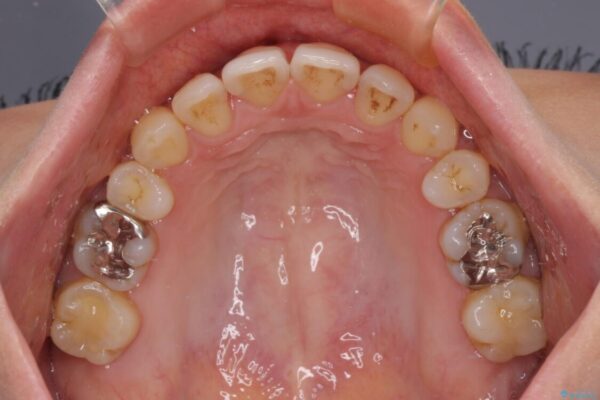

上の前歯の突出感を気にして来院された患者様です。

目立たない装置を希望とのことで、上顎左右第一小臼歯を抜歯し、インビザラインにて矯正治療を行うこととしました。

治療前

• 上顎前歯の突出を軽減 インビザラインによる抜歯矯正 治療前画像